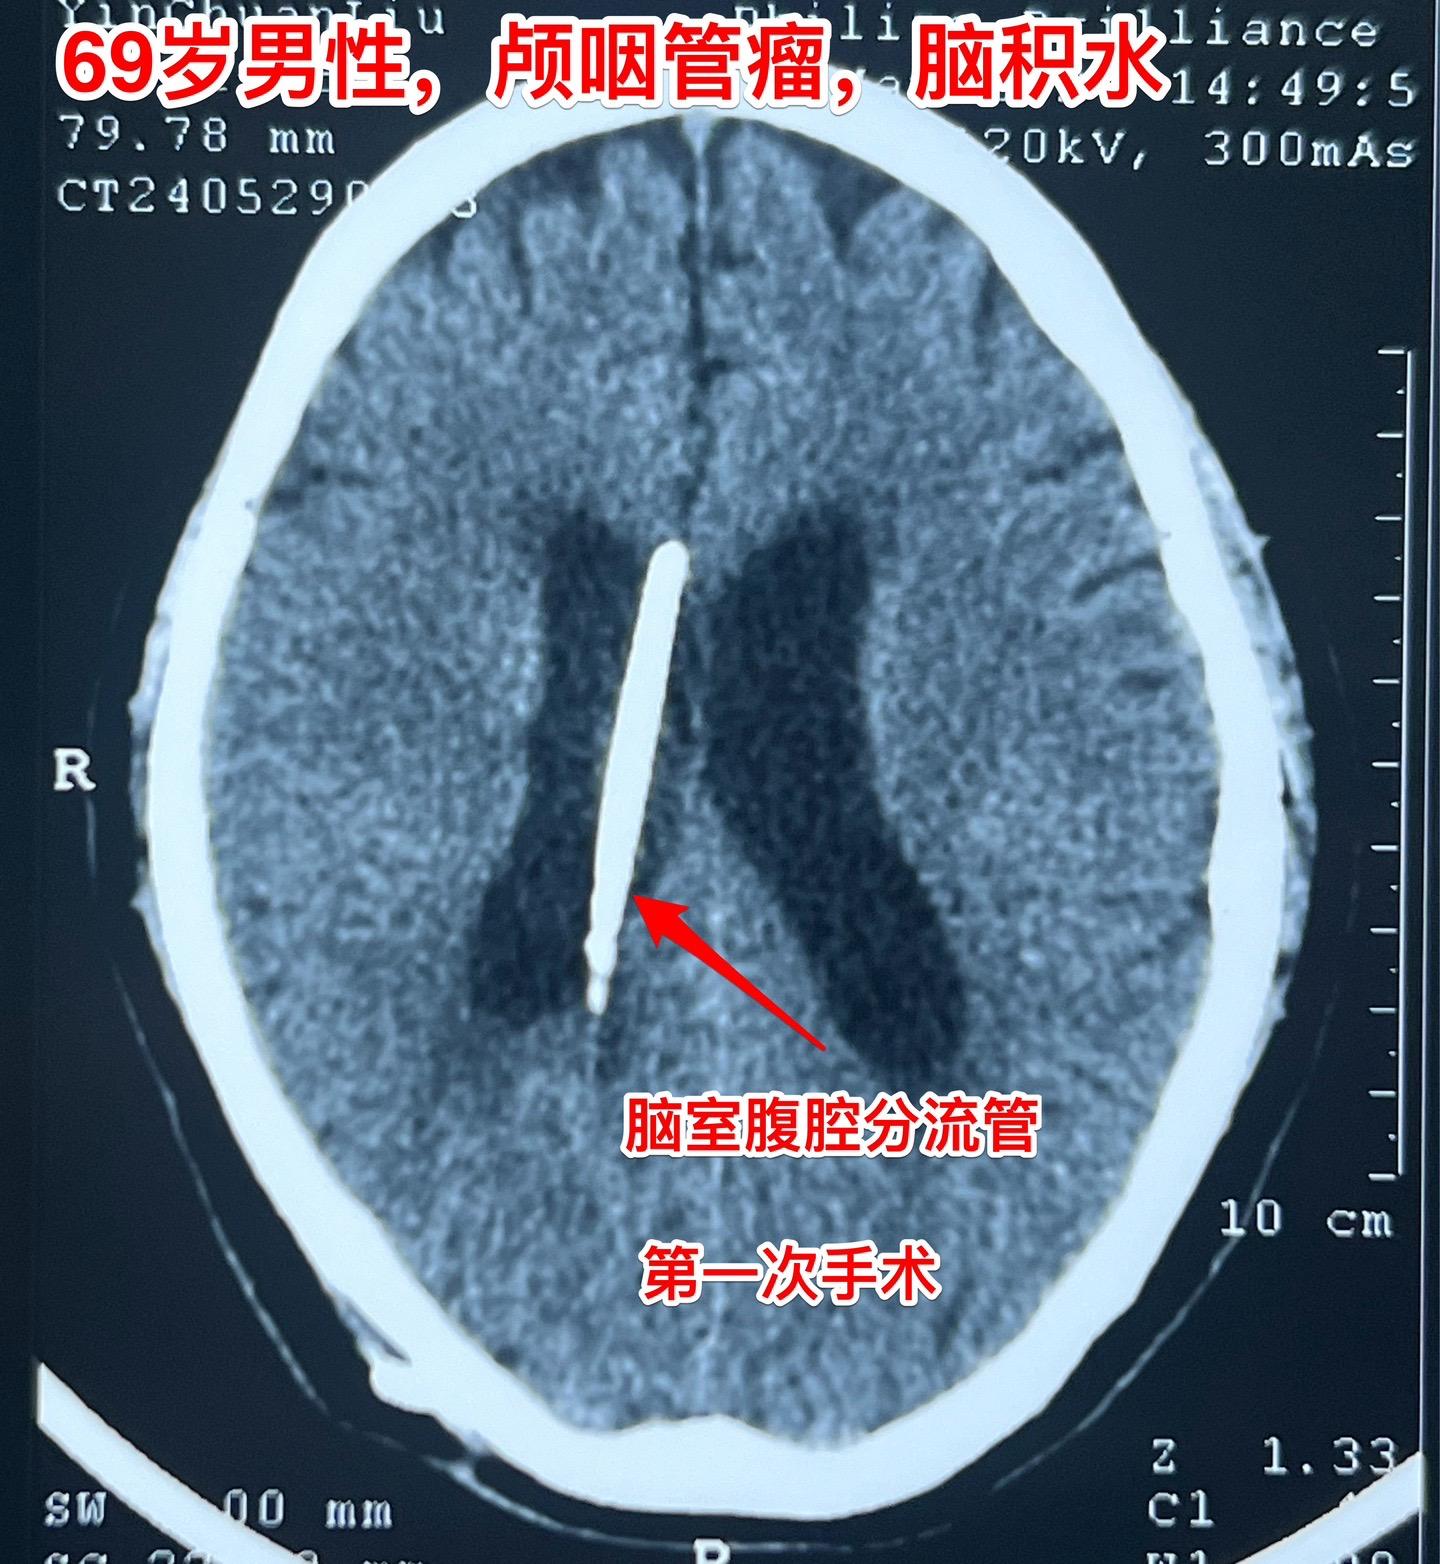

69岁发现颅咽管瘤还能作手术吗?69岁的南通市老人近半年出现记忆力差、糊涂。4月份出现尿失禁,到医院检查才发现病根儿是颅咽管瘤,肿瘤体积大,导致了脑积水。第一步在当地医院先作了脑室-腹腔分流术,治疗脑积水,尿失禁的症状有改善。 但是老人的身体很虚弱。还不能下地行走。这样的身体状态是不能承受切除颅咽管瘤这样的大手术的。 老人的女儿随后和我加后,我给予老人补充激素后,老人的身体状况才逐步改善,慢慢地能下地走路了。 不能不佩服这家人的勇气和爱心[强][强]!